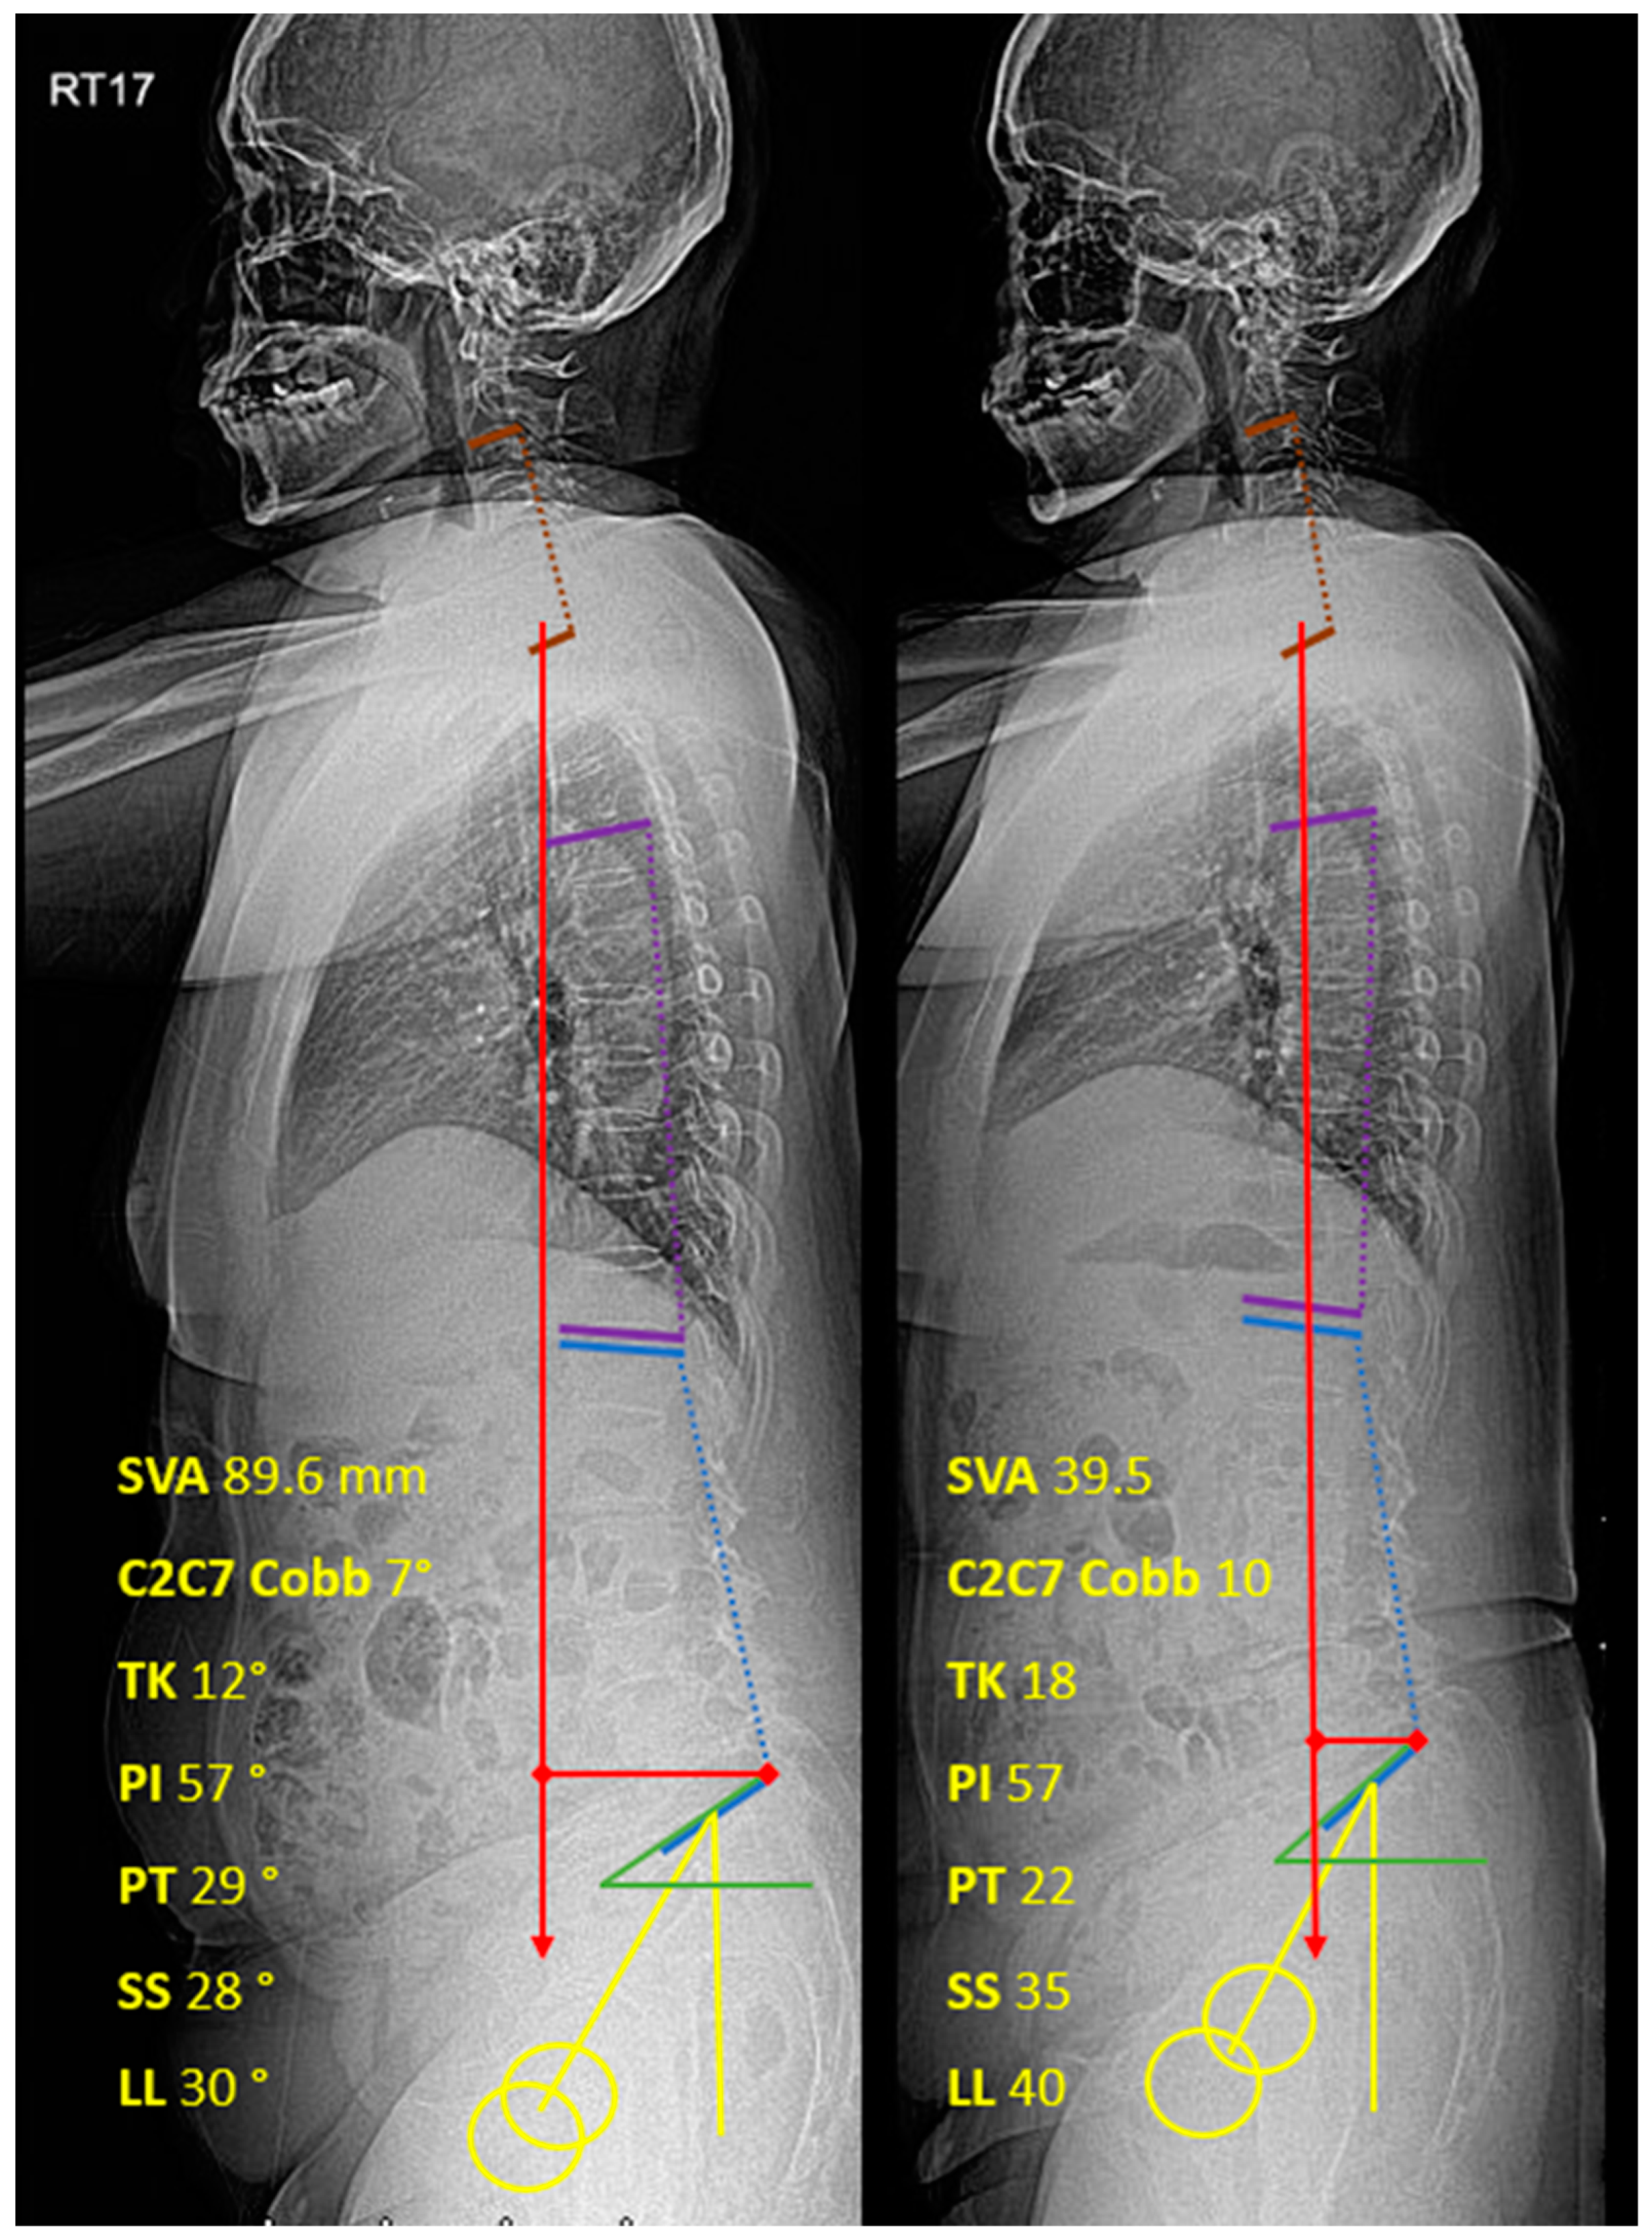

TFESI was performed with triamcinolone acetonide 40mg/1cc (40 mg for one-level injection and 80 mg for 2 to 4 levels injections) and normal saline mixed up to 2 cc for each injection point. In addition, Iohexol (Omipaque 300 Contrast) 0.5-1 cc was administered as a contrast media to confirm the position prior to steroid injection under biplanar (AP and lateral) fluoroscopic guidance (C-arm Fluoroscope, Philips BV Pulsera). Quincke spinal needles size 23 gauge 9 cm were used and they were angled towards the safe triangle [21,22] in the AP view and towards the middle of the neural foramen in the lateral view (Figure 2).

Figure 2. (A) AP Fluoroscopic view. The end of the needle is located in a safe triangle. (B) Lateral Fluoroscopic view. The end of the needle is located in the middle of the neural foramen. (C) Lateral Fluoroscopic view. After the L4 nerve root contrast injection was outlined.